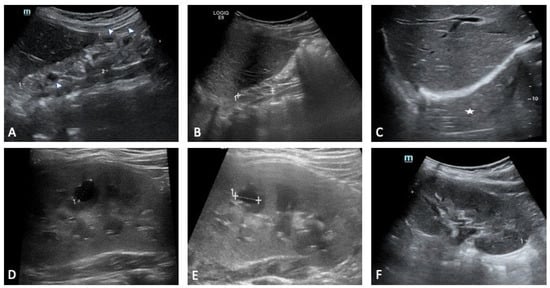

Renal involvement is the most frequent and recognisable manifestation of the deletion, and it provides a paradigmatic example of how structure and function diverge. Our three siblings vividly illustrate the breadth of renal involvement associated with the deletion. The eldest showed marked congenital abnormalities, with a multicystic right kidney evident from the prenatal period. Serial ultrasound demonstrated progressive atrophy of the right kidney until it became no longer visible, leaving an empty perirenal space, while the left kidney underwent clear compensatory hypertrophy. The renal parenchyma remained diffusely hyperechoic with absent corticomedullary differentiation, and small cortical cysts appeared in both kidneys. Additional urinary tract anomalies included a dysmorphic septate gallbladder, a bladder diverticulum and distal ureteral ectasia, all of which contributed to the complexity of the renal picture. Despite these abnormalities, renal function declined only gradually and stabilised with careful monitoring.

The second sibling had a milder presentation. Early scans showed bilateral multicystic involvement, with the left kidney more affected, although renal function was preserved. Mild proteinuria and phosphaturia appeared intermittently but resolved without specific intervention. By the age of five years, renal imaging had normalised, and serum creatinine and electrolytes remained within expected limits.

The youngest sibling had prenatal signs of right kidney hyperechogenicity and bilateral pyelectasia. These changes improved over time, and renal function remained stable across follow up. Occasional proteinuria and phosphaturia were noted in early life, although subsequent biochemical tests showed steadier values. Compared with the older sibling, the renal course was relatively uncomplicated, despite the early anatomical findings (Figure 3, Figure 4 and Figure 5).

Figure 3. Sibling 1. Abdominal ultrasound examinations were performed at 3 (A,D), 4 (B,E), and 7 (C,F) years of age. (AC) show progressive right kidney atrophy [maximal pole-to-pole diameter approximately 49 mm (dotted line 1 in (A)) and 33 mm (dotted line 1 in (B)); in (C), the right kidney is not clearly identifiable at the ultrasound exam («empty perirenal space», white asterisk)]. Renal parenchyma structure is altered, diffusely hyperechoic, with no clear differentiation between cortex and medulla (A,B). Some small cystic lesions can also be noted (arrowheads in (A)). Dotted line 2 in (A): antero-posterior diameter (20 mm). (DF) show progressive compensatory hypertrophy of the left kidney [maximal pole-to-pole diameter approximately of 78 mm, 85 mm and 93 mm, respectively (the latter shown as dotted line 1 in (F))]. Some cystic lesions are identified in the renal parenchyma, with the most prominent of around 10 mm located in the middle third (dotted lines 1 in (D,E)).

Figure 4. Sibling 2. Abdominal ultrasound exam performed at 5 years of age; images exploring the right (A) and left (B) perirenal spaces of the abdominal cavity. (A) shows a normal-sized kidney [pole-to-pole diameter approximately 79 mm (dotted line 1), anterior parenchymal thickness of 17 mm (dotted line 2)], with normal echogenicity. On the other hand, the left kidney structure is diffusely altered with several cysts seen within, ranging in size from a few millimeters to some centimeters (the most prominent one approximately measures 81 mm × 91 mm in the sagittal plane (dotted lines 1 and 2 in (B)).